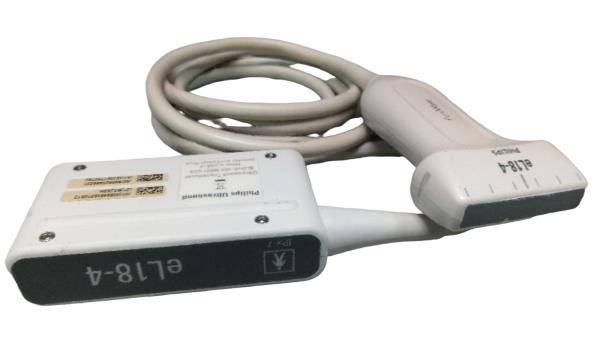

DIAGNOSTIC ULTRASOUND MACHINES FOR SALE

CS-ECG120MX Medical Replacement for CMICS

Sale price$ 328.00